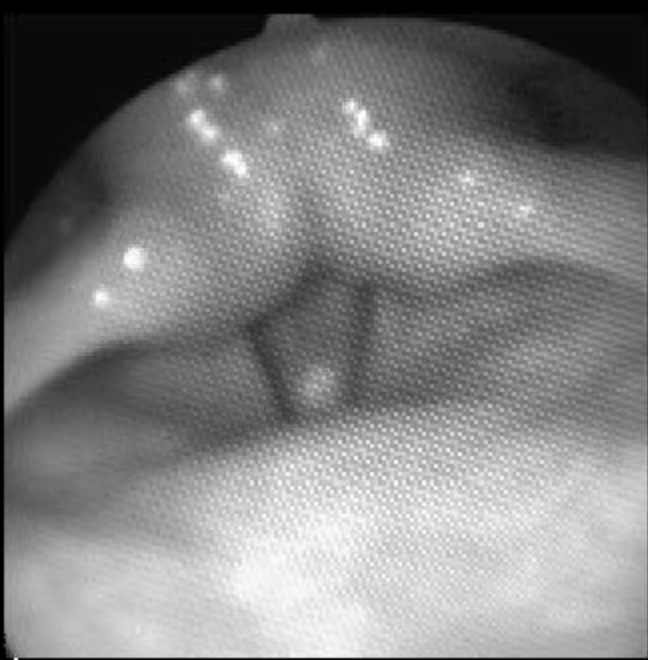

川原 そうそうそう、すごく良い。「か」と「が」の違いは、のどの話みたいだね。MRIの次はこちらを見てみよう。性能の良いカメラが先にくっついたファイバースコープを鼻の穴から通して、のどで何が起こっているのかを写す機械があるんだ。

これで声帯っていうのを写せる。「声帯」って聞いたことがあるんじゃないかな。

藤田先生 なった、なった。

川原 ありましたよね。みんなも聞いたことがあるかもしれないけど、その「声帯にポリープができる」というのはここなの。みんなが声を出すときに、喉の奥で震えて音をだしてくれているものがあるのよ。この声帯がどうやって震えているかっていうのをハイスピードカメラで撮りました。「えけ」って発音しているときと「えげ」って発音しているときの動画を見せるね。上が背中側で、下がのど側です。右と左に1枚ずつ声帯がついているのが見える?

まず「え」って発音しているとき。2枚の声帯が、震えているでしょう? ここから「け」が始まります。どうなった?

川原 そう、声帯の震えが止まっているでしょう? 2枚の声帯がだんだん開いていっているのわかる?

川原 そう。すごく大きく開いているでしょう? ずっと開きつづけて、ここで2番目の「え」(「け」の「え」)が始まります。「え」が始まると、また声帯が閉じて震えているでしょう?

私たちの喉の奥には声帯が2枚あって、声を出すときって基本的に震えて音を出してくれています。でも、「け」って言うときには声帯が広く開いていて震えないのよ。じゃあ、「えげ」の時はどうなっているのかを見てみようね。

ここは「母音」の部分。「母音」って言っちゃ駄目だ、みんなには伝わらないものね。初めの「え」の部分。前と同じように震えているね。そして「げ」に入ります。ほら、さっきの「け」の時と違っているのがわかる?

―― うん、揺れてる。

―― ずっとぱくぱく。

川原 そう、ずっとぱくぱくしているの。ということは、「か」と「が」は何が違うんですかっていうと、「かきくけこ」のときは声帯が開いて震えなくなっちゃう。だけど、点々が付くと声帯が震えます。「かきくけこ」は「『すんって』すかしている」ってはるまが言ってくれたじゃない? 「かきくけこ」は声帯が震えないから「すっ」と空気が流れる感じがしたのかな? それに対して「がぎぐげご」のときは、ずっと声帯が震えていて「ずーん」としている感覚があったのかなって思いました。